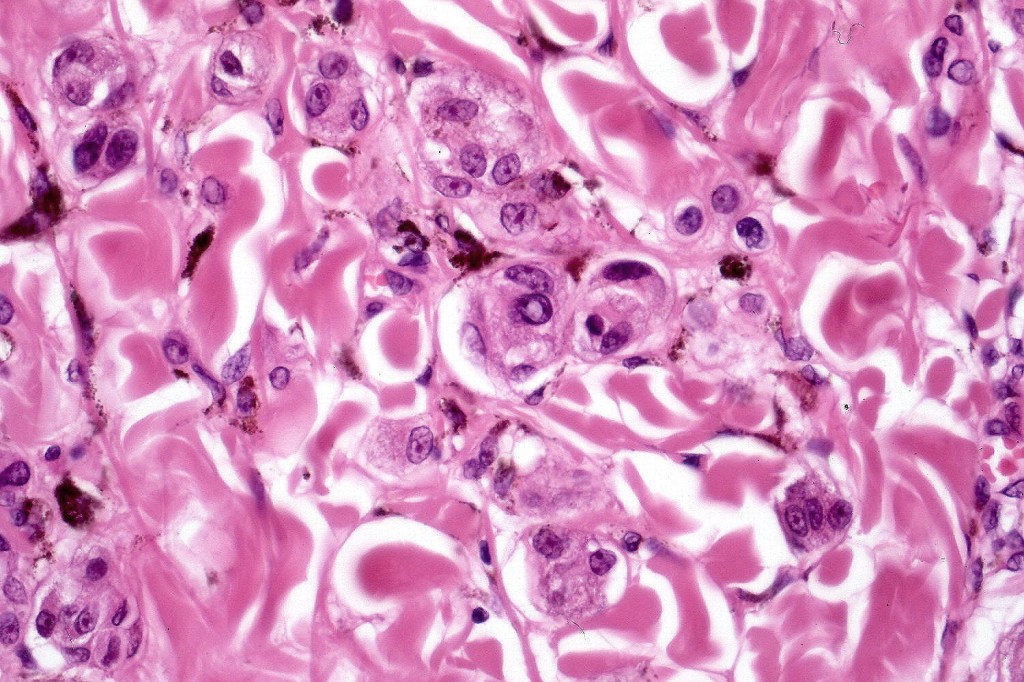

•Superficial epithelioid cells

•Deep spindle cells

•Focal atypia (enlarged, hyperchromatic nuclei)

•Clear cells

•Dendritic cells

•Melanophages

•Multinucleate giant cells

• Cytoplasmic intranuclear pseudo-inclusions, small eosinophilic nucleoli

•Occasional mitoses